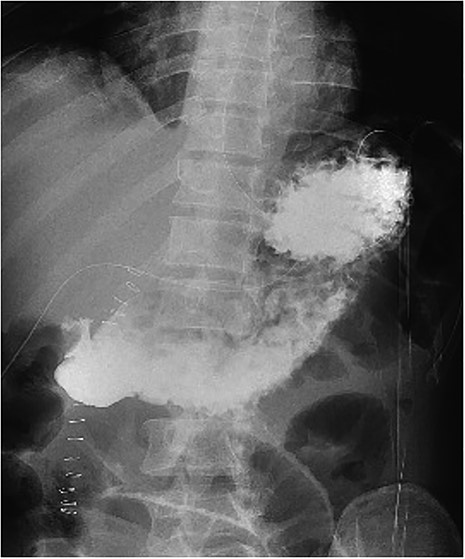

The patient was transferred to the surgical ward for ongoing cares, remaining nil by mouth and commenced on intravenous antibiotics and proton pump inhibitor infusion. On post-operative day 3, a follow-through contrast study showed no leak of enteric contents from the stomach (Fig. 3) with transit of the contrast into the duodenum, and a concurrent ileus was shown with prominent small bowel loops (Fig. 4). A clear fluid diet was initiated, with gradual upgrade before discharge to usual residence and follow-up gastroscopy as outpatient.